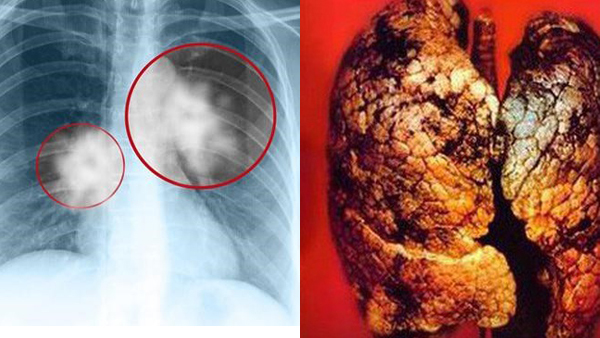

Bệnh nhân được xác định mắc bệnh mô bào ở phổi giai đoạn cuối (Langerhans) - một dạng bệnh ung thư rất đặc biệt, bệnh tự miễn, không có phương pháp điều trị triệt để.

Trên phim chụp cắt lớp ngực, gần như toàn bộ tổ chức phổi của bệnh nhân đã bị tiêu huỷ hết các thành nang – kén khí, không còn hoạt động chức năng.